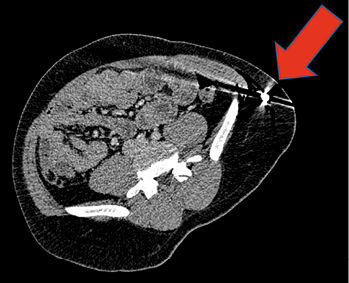

Der Patient war wach, fixierte und kommunizierte adäquat verbal. Er war voll orientiert und konnte sich an das genaue Unfallereignis erinnern. Zu Bewusstlosigkeit war es im Rahmen des Unfallereignisses nicht gekommen. Der Arbeiter berichtete, dass er auf der Baustelle einen Schritt nach hinten gegangen war und daraufhin auf einer Folie, die um den Rand der Baugrube ausgelegt war, ausgerutscht sei. Er sei in der Folge etwa einen Meter tief in die Grube gefallen und habe daraufhin einen starken Schmerz in der linken Flanke verspürt. Hierbei war es zu einer Pfählungsverletzung des Abdomens durch einen herausragenden Stahlstab von 8 mm Dicke gekommen (   Abb. 1 ).

Das eingedrungene Ende des Stahlstabes führte zu einer deutlich sicht- und tastbaren Vorwölbung im linken Unterbauch, die Haut stand hier unter starker Spannung. Das Abdomen war weich, es bestand keine Abwehrspannung. Ein Wiederaustritt des Stahlstabes wurde nicht festgestellt. Die Eindringtiefe des Stahlstabes wurde vor Ort auf ca. 15–20 cm geschätzt. Die sichtbare Blutung war im Bereich der Eintrittswunde minimal. Im Rahmen der Erstuntersuchung des Patienten wurden neben der beschriebenen abdominellen Pfählung keine weiteren Verletzungen festgestellt. Wegen der Art der Verletzung und der damit verbundenen Erfordernis der technischen Rettung wurde die Feuerwehr nachgefordert.